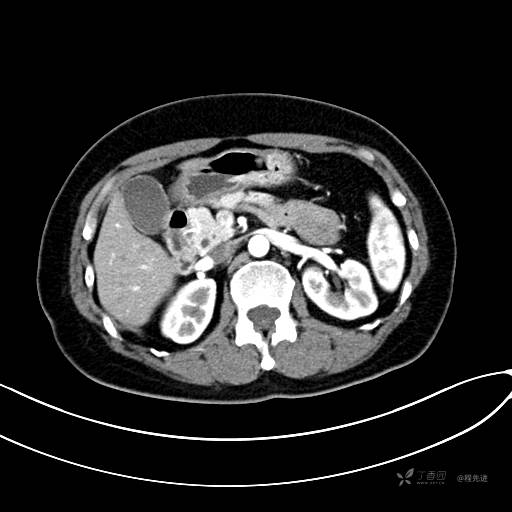

CT增强静脉期